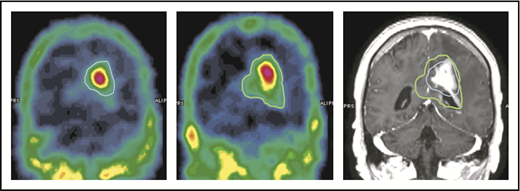

The capability of NGR-hTNF to increase vascular permeability in tumor and perilesional areas was confirmed by results of SPECT studies. Quantitative analysis showed an increase in the extent of the 99mTc-DTPA–positive region(s) in all the investigated cases (an example is given in Figure 5). The median volume of ≥30% 99mTc-DTPA uptake (volume of interest) measured before and after the infusion of NGR-hTNF/R-CHOP was 26 cm3 (range, 5-67 cm3) and 40 cm3 (range, 10-92 cm3), respectively (P = .028). There was a median volume increase of 45%, with a range of 14% to 87%.

An example of increase of 99mTc-DTPA uptake after the infusion of NGR-hTNF followed by R-CHOP at the third course of treatment. The volume of ≥30% 99mTc-DTPA uptake is contoured in 2 SPECT studies performed before (left image, blue line) and after (middle image, green line) administration of NGR-hTNF and R-CHOP. Comparison of contoured volumes are represented in the gadolinium-enhanced T1-weighted MRI showing the tumor (right image). The volume of interest before and after NGR-hTNF/R-CHOP delivery was 22 cm3 and 40 cm3, respectively.